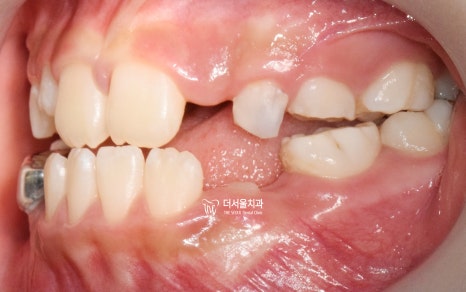

『페이스 마스크(face mask) 사용』

착용 전

착용 후

악궁 확장장치와 페이스마스크를 사용했습니다.

그렇게, 페이스 마스크 및 악궁확장장치를

끼니 윗니가 아랫니가 덮는 overjet 이

형성 되어있는 것을 볼 수 있네요.